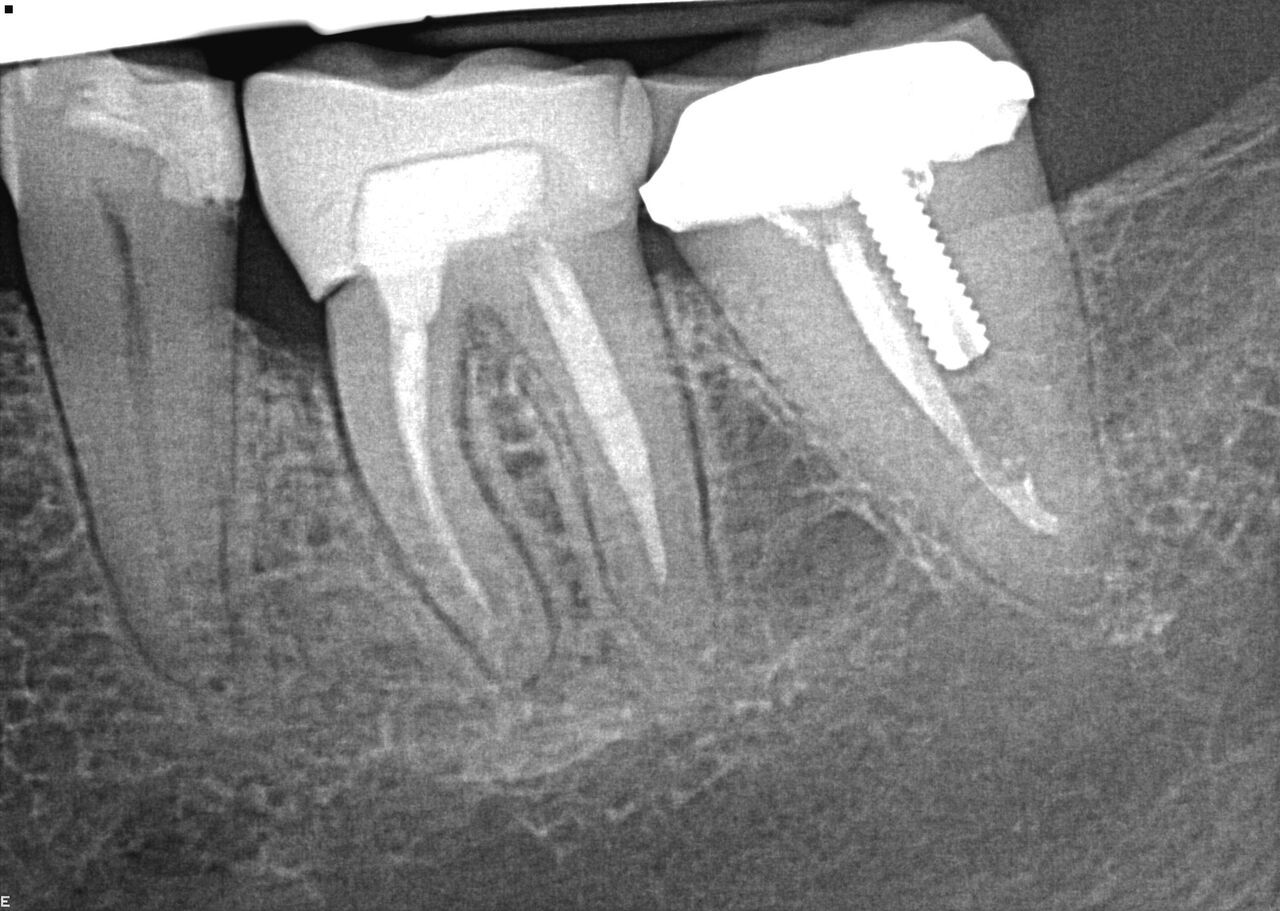

(8.) Case 2 initial radiograph of Nos. 12 through 14 with disunion of No. 12 crown to underlying root.

Figure 8

( 9.) Case 2 initial radiograph of Nos. 12 through 14 with disunion of No. 12 crown to underlying root.

Figure 9

A 67-year-old woman presented on an emergency basis with a bad odor and taste from crown No. 12, which had been diagnosed that day at hygiene recall as decayed and no longer attached to the underlying root (Figure 8 and Figure 9). The patient was anesthetized and the existing bridge was sectioned (Figure 10), leaving crown No. 14 intact. The No. 12 root was extracted and the site was fully debrided of granuloma. A platform shift implant was stabilized in excess of 45 Ncm in position No. 12, which was prosthetically correct. The soft tissue of pontic site No. 13 was contoured to mimic soft tissue contours of a bicuspid and an implant was secured in excess of 45 Ncm. Implant No. 13 was milled to allow for unimpeded seating of the temporization abutment, whereas implant No. 12 did not need milling as it was a platform-shift implant. The existing crown No. 12 and cantilever No. 13 were revised to be a temporary bridge on Nos. 12 and 13 (Figure 11 and Figure 12). The revised temporary bridge was positioned in infraocclusion and cemented after the extrusion of excess cement extraorally (Figure 13). No bone graft or sutures were placed as the temporary crowns sealed the sockets.